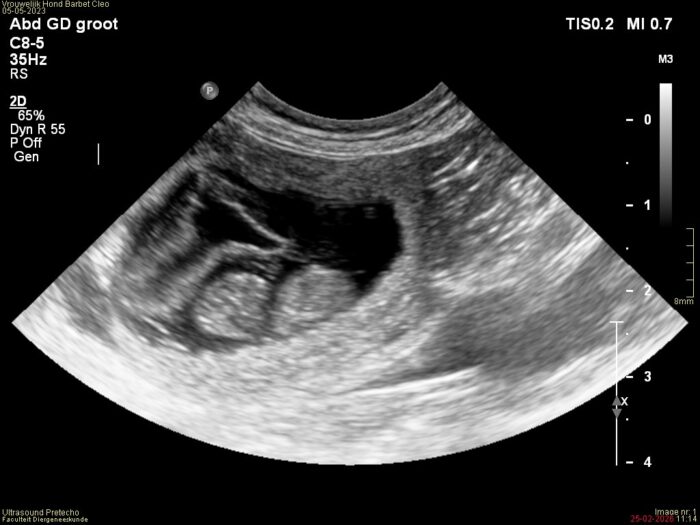

Tussen dag 26 en 32 kan palpatie plaatsvinden: het uitwendig voelen met de hand of de teef drachtig is. Tussen dag 28-35 kan de echo plaatsvinden.

Vandaag is het eindelijk zover. Het is 4 weken na de dekking en vandaag zijn we weer naar de dierenarts gegaan. Eenmaal aangekomen werd Cleo wederom begroet door het fertiliteitsteam van de dierenkliniek.

Na het beantwoorden van wat vragen, was het aan een ieder om eerst uitwendig met de hand voelen. Op de vraag of Cleo drachtig is of niet, moesten we nog even wachten tot iedereen had gevoeld. En toen de dierenarts zelf ging voelen, kwam daar het verlossende antwoord: ze is drachtig! Ook Saskia en ik konden het nu goed voelen. Heel bijzonder om dit zo te kunnen doen.

Daarna is er een echo van de buik gemaakt. Een zeer uitgebreide echo waarbij alles heel duidelijk in beeld is gebracht. En toen was daar een kloppend hartje met geluid! Wat is en blijft dat toch een bijzonder moment om dat geluid te mogen horen. Een krachtig hartje van zo’n minuscuul pupje in wording. Want dat is het; de embryo’s zijn nu ca 1,5 cm groot en zien er nu nog uit als een soort pinda. Over een week hebben ze al een ruggengraat, pootjes, een kop en een staart. Het zal zich nu in een razend tempo gaan ontwikkelen. Geen wonder dat Cleo moe is, veel slaapt en minder eetlust heeft. Gelukkig gaan we op naar week 5 en dat betekent voor Cleo dat ze zich langzaam beter zal gaan voelen.